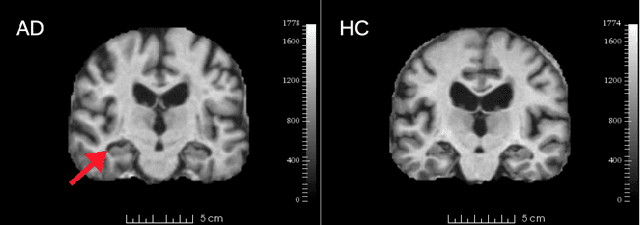

This paper proposes a principled information theoretic analysis of classification for deep neural network structures, e.g. convolutional neural networks (CNN). The output of convolutional filters is modeled as a random variable Y conditioned on the object class C and network filter bank F. The conditional entropy (CENT) H(Y |C,F) is shown in theory and experiments to be a highly compact and class-informative code, that can be computed from the filter outputs throughout an existing CNN and used to obtain higher classification results than the original CNN itself. Experiments demonstrate the effectiveness of CENT feature analysis in two separate CNN classification contexts. 1) In the classification of neurodegeneration due to Alzheimer's disease (AD) and natural aging from 3D magnetic resonance image (MRI) volumes, 3 CENT features result in an AUC=94.6% for whole-brain AD classification, the highest reported accuracy on the public OASIS dataset used and 12% higher than the softmax output of the original CNN trained for the task. 2) In the context of visual object classification from 2D photographs, transfer learning based on a small set of CENT features identified throughout an existing CNN leads to AUC values comparable to the 1000-feature softmax output of the original network when classifying previously unseen object categories. The general information theoretical analysis explains various recent CNN design successes, e.g. densely connected CNN architectures, and provides insights for future research directions in deep learning.